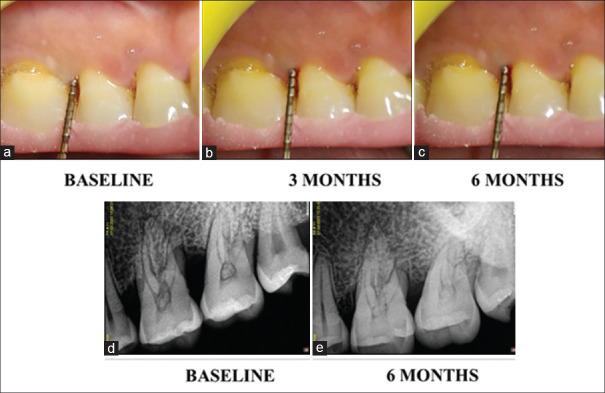

Background and objectives: Many Ayurvedic and herbal medications are used to overcome the drawbacks of allopathic medications. The objective of the current study was to assess and contrast the osteoanabolic effects of Picrorhiza kurroa and F. bengalensis gel on the quantity of bone fill in Stage III periodontitis using Radiovisiography (RVG).

Materials and methods: In the present split-mouth trial, 44 bilateral intrabony defects (IBDs) were randomly assigned to two groups. Group I received nonsurgical periodontal therapy (NSPT) alone, whereas Group II received NSPT along with Picrorhiza Kurroa and Ficus Bengalensis gel. The IBD fill using RVG was the primary outcome measurement and secondary outcomes were probing pocket depth, clinical attachment level, plaque index, and modified sulcus bleeding index reported at baseline, 3 months, and 6 months.

Results: Both the study groups exhibited improvements in the measurements that were evaluated, although Group II significantly outperformed Group I in terms of IBD fill and clinical parameters.

Conclusion: As a supplement to NSPT, the use of picrorhiza kurroa and ficus bengalensis gel is more advantageous in obtaining superior clinical and radiographic outcomes after 3 and 6 months.